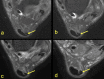

The aim of the study was to check if the subtendons of the Achilles tendon can be identified in vivo on MRI in the midportion of the tendon. The relation of the plantaris tendon to the Achilles tendon was also examined. A retrospective study of 200 MRI of ankle joints including the Achilles tendon was conducted. Statistical analysis of the correlation between the possibility of identifying the subtendons and the side, gender, presence of the central soleus tendon and plantaris tendon variation was performed. The inter-observer agreement between two reviewers in their evaluation of the subtendons was assessed using kappa statistics. The subtendon from the lateral head of the gastrocnemius muscle was identified in 65% (k = 0.63) and was located in the anterior part of the Achilles tendon. The subtendon from the soleus muscle was recognized in 12% (k = 0.75) comprising anterior part of the tendon. In 6% the subtendon from the medial head of the gastrocnemius muscle was identified (k = 0.58). The central soleus tendon was identified in 85% of cases. Statistical analysis shows the weak correlation of the presence of the central soleus tendon and the possibility of identifying the subtendon from the soleus muscle. The plantaris tendon was directly related to the insertion of the Achilles tendon in 42.5%. Identification of the subtendons of the Achilles tendon on MRI is challenging, and most often it is only possible to find the subtendon of the lateral head of the gastrocnemius muscle.